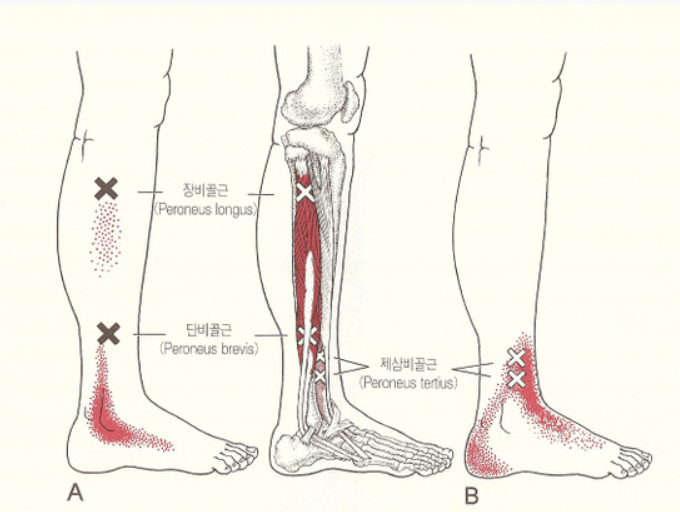

족저근육 긴장 및 피로

오랜 시간 서 있거나 걷는 활동, 또는 무리한 운동 후 근육이 경직되면서 일시적인 발바닥 통증이 생깁니다. 이 경우는 휴식과 스트레칭, 온찜질로 회복이 가능하며, 만성화되면 근막염으로 발전할 수 있습니다.